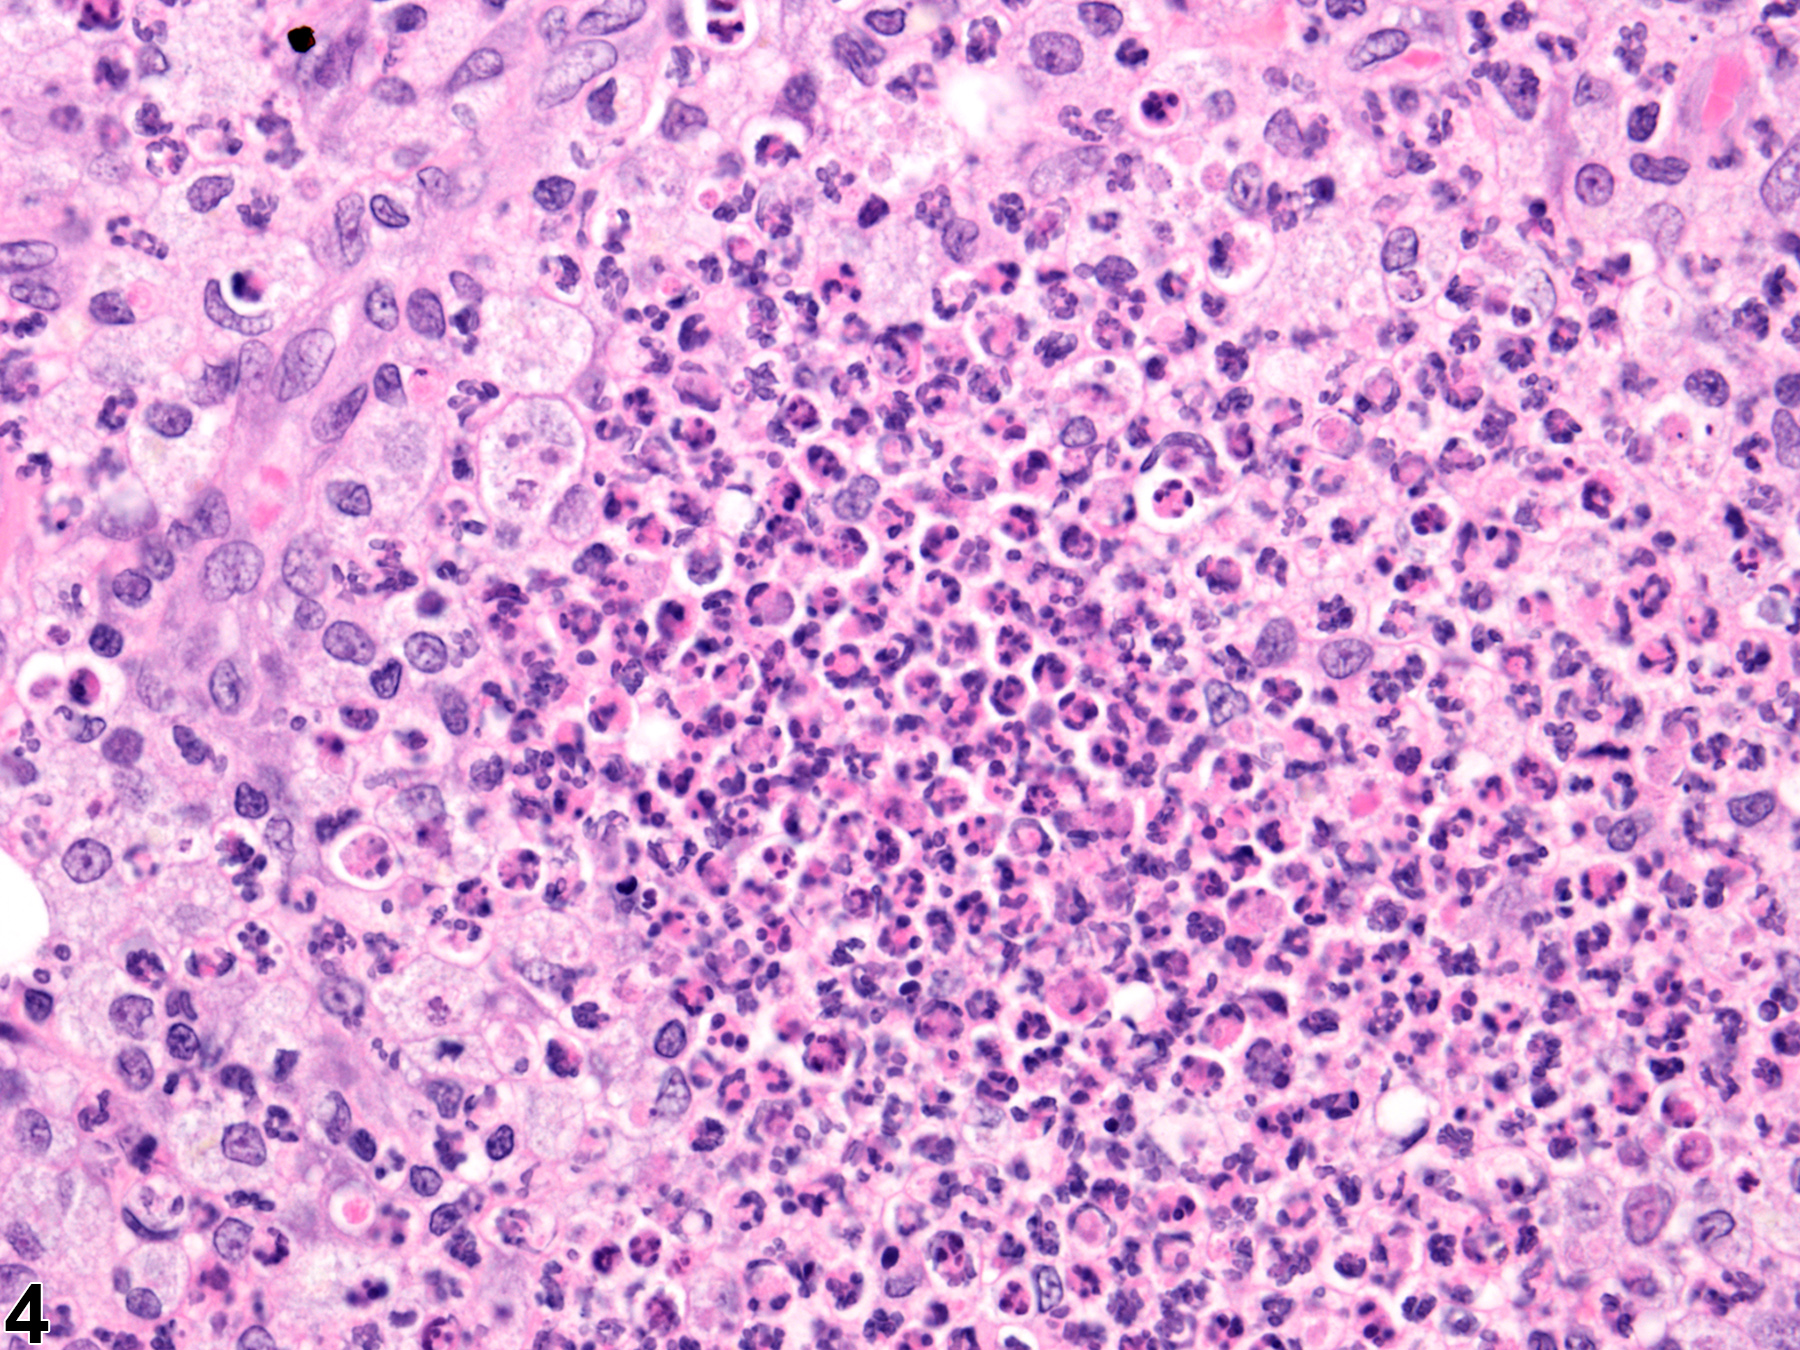

Acute inflammation (Figure 1 and Figure 2) in the mammary gland is characterized by infiltration of neutrophils, which may be accompanied by eosinophils and, to a lesser extent, macrophages, mast cells, lymphocytes, and plasma cells. These cellular infiltrates are generally accompanied by vascular congestion; edema; the accumulation of serous, mucous, or fibrinous exudates; and sloughed epithelial cells in tubular and/or alveolar lumina. Suppurative inflammation (Figure 3 and Figure 4) of the mammary gland is characterized by discrete pockets of degenerate neutrophils and cellular debris. Evidence of chronicity, such as fibrosis and lymphoplasmacytic infiltrates, may also surround these pockets. Chronic inflammation of the mammary gland is characterized by the presence of mononuclear cells (lymphocytes, plasma cells, and macrophages) and may be accompanied by epithelial cell regeneration, hyperplasia and/or metaplasia, and fibrosis. Chronic active inflammation of the mammary gland is characterized by the coexistence of elements of chronic inflammation (lymphocytes, macrophages, regeneration, hyperplasia, and fibrosis) and superimposed acute inflammation (neutrophilic and/or eosinophilic). Granulomatous inflammation is characterized by an accumulation of plump macrophages (epithelioid cells) organized in interlacing bundles, with variable numbers of multinucleated giant cells, lymphocytes, plasma cells, or neutrophils and may be accompanied by fibrosis epithelial cell regeneration, hyperplasia, and/or metaplasia. Granulomatous inflammation is commonly seen in rats associated with rupture of dilated ducts. Other etiologic agents may be present and induce inflammatory changes (e.g., fungi, foreign bodies, etc.). All forms of inflammation may be accompanied by associated lesions, including edema (though this is more commonly associated with acute inflammation), epithelial hyperplasia, neovascularization, or hemorrhage with or without hemosiderin-containing macrophages.

Mammary gland - Inflammation, chronic active in a female B6C3F1/N mouse from a chronic study. Mammary gland inflammation (featuring infiltrates consisting mainly of neutrophils) is located primarily in the stroma between alveoli.